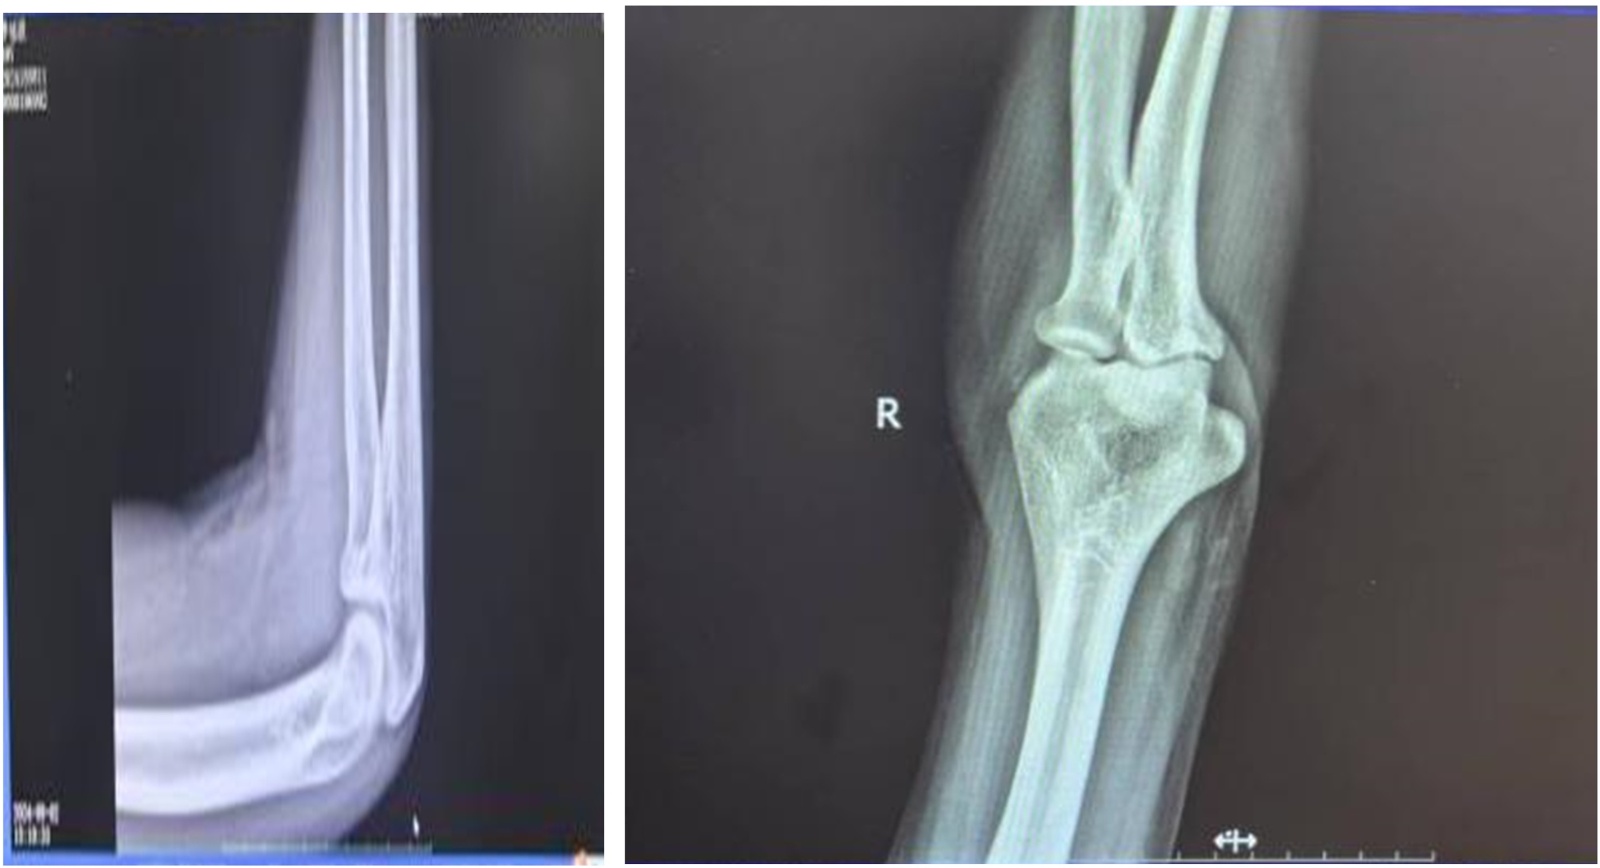

Figure 2. Post-reduction X-ray image of ulnar coronoid fracture

2. 冠骨折复位后X线图像

患者,男,50岁,于2024年7月踢球运动中跌倒后出现右肘及右腕部肿胀疼痛伴活动受限就诊。骨科检查:一般情况好,神清,右肘皮肤有轻度擦伤,右肘关节肿胀,屈伸活动严重受限,被动活动时疼痛加重。肘关节x线检查提示:右侧尺骨冠状突局部骨皮质撕裂,可见多个小骨碎片并有移位,肘关节不全脱位,右侧桡骨小头和右侧肱骨远端未见骨折征象,右侧尺骨冠突骨折(见图1)。诊断:尺骨冠突骨折。治疗方法:1. 门诊以行手法复位,复位手法:前臂旋后位,一手扶患肢肘部,拇指置肘窝,摸清向上移位骨折块,垂直向下按压,同时屈曲肘关节,使前臂旋后,屈肘100˚位肩肘带固定于胸前。复位后患者自觉肘关节疼痛较前明显减轻,遂行x线复查可见尺骨冠突对位对线情况良好(见图2)。2. 局部金黄膏外敷消肿止痛[3],日更换一次。制动2周后行肘关节行屈伸功能锻炼,局部中药透入治疗。

治疗结果:6周后(见图3)患者复查X线影像显示骨折对位愈合良好,前臂旋转及曲肘功能可,5月(见图4)后复诊患者功能恢复正常。